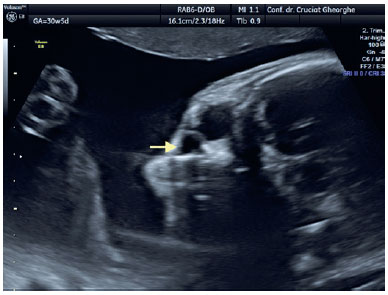

Examination of the fetal cephalic pole using fetal ultrasound performed at 31 WG revealed the presence of a 3-mm, liquid-filled, hypoechoic cyst located inferiorly and separated from the right eye ball (Figure 1). At 33 WG, the cystic lesion had enlarged (6/4.5 mm); however, it remained well demarcated from the eye ball and the nasal fossa. At the 36 WG follow-up examination, the dimensions of the right cyst were 8/7 mm and a similar lesion of 6/4.5 mm was identified contralaterally (Figure 2). At 38 WG, the DCC on the left side diminished and its content became more dense/opaque, whereas the structure on the right side maintained its liquid content and increased in size to 8/8.5 mm (Figure 3). All ultrasound examinations were performed using a Voluson E8 ultrasound system (GE Medical Systems, Zipf, Austria). Elective Cesarean section was performed at 39 WG, without perioperative complications. The newborn weighed 3,800 g, with an Apgar score of 10.